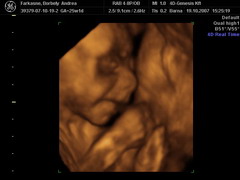

Megpróbáltam vonalzót készíteni remélem sikerül. Ha tudok, és nem bánjátok teszek fel 4d képet, de lehet, hogy ehhez már apára lesz szükségem.